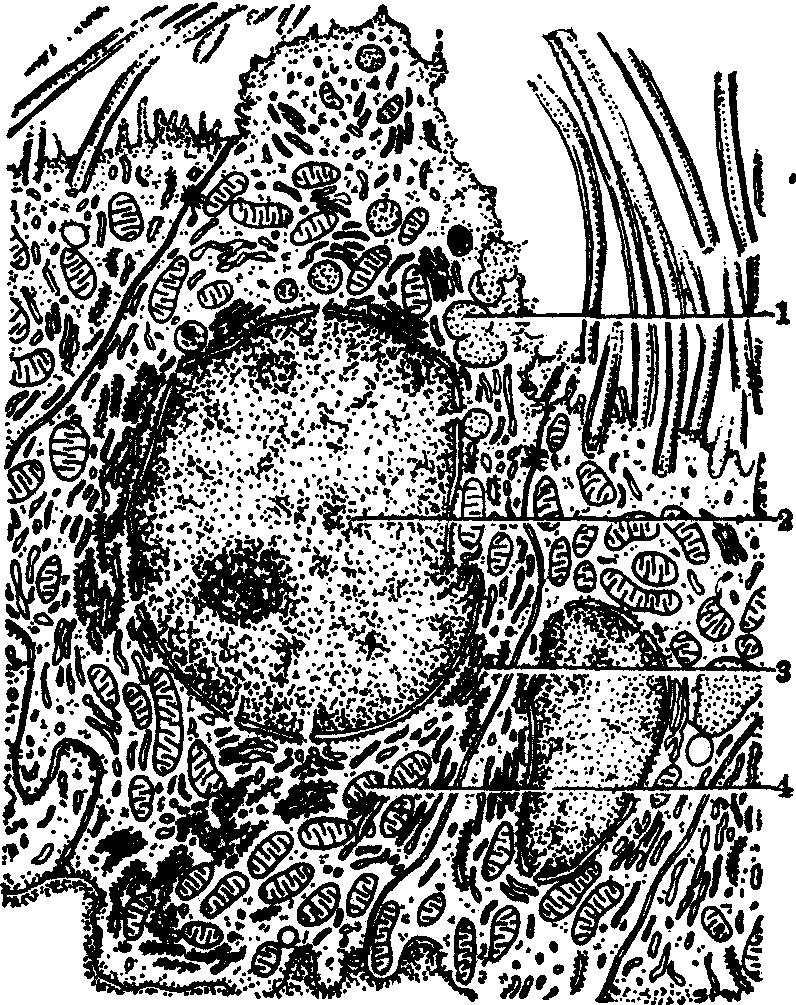

哺乳类肺的导气部和呼吸部示意图

1. 气管; 2. 支气管;3. 细支气管和终末细支气管;4.呼吸性细支气管; 5.肺泡管; 6. 肺泡囊; 7. 肺泡

肺的组织结构 表面覆有一层浆膜,即肺胸膜。结缔组织伸入肺,将肺组织隔成许多肺小叶,呈锥体状,尖朝向肺门,底朝向肺表面。小叶间的结缔组织和肺泡隔组成肺的间质,内有血管、淋巴管和神经等。肺实质由导气部和呼吸部组成(见图)。导气部为左、右大支气管从肺门入肺后,反复分支而成的支气管树,包括小支气管、细支气管、终末细支气管。终末细支气管以下的分支为肺的呼吸部。由一支细支气管反复分支形成肺小叶内的导气部和呼吸部。

支气管由肺门入肺后反复分支形成支气管树。支气管分支在直径1mm以下的称细支气管;细支气管分支直径到0.5mm时称终末细支气管。从肺内支气管至终末细支气管为肺的导管部。终末支气管以下的分支,包括呼吸性细支气管、肺泡管、肺泡囊及肺泡为肺的呼吸部(图1、图4)。每一细支气管连同它所属的分支与肺泡共同构成肺小叶。肺小叶呈锥形,锥尖朝向肺门,锥底朝向肺表面。各小叶间有薄层结缔组织分隔。

图1 人肺结构(低倍光镜)模式图

1.腺 2.支气管 3.支气管动脉 4.上皮 5.平滑肌 6.软骨 7.平滑肌 8.肺泡管 9.细支气管 10.肺动脉 11.肺静脉 12.肺泡囊 13.呼吸性细支气管 14.肺泡管 15.肺泡 16.尘细胞

图4 肺呼吸部模式图

1.呼吸性细支气管 2.肺泡孔 3.肺泡管 4.肺泡 5.肺泡囊